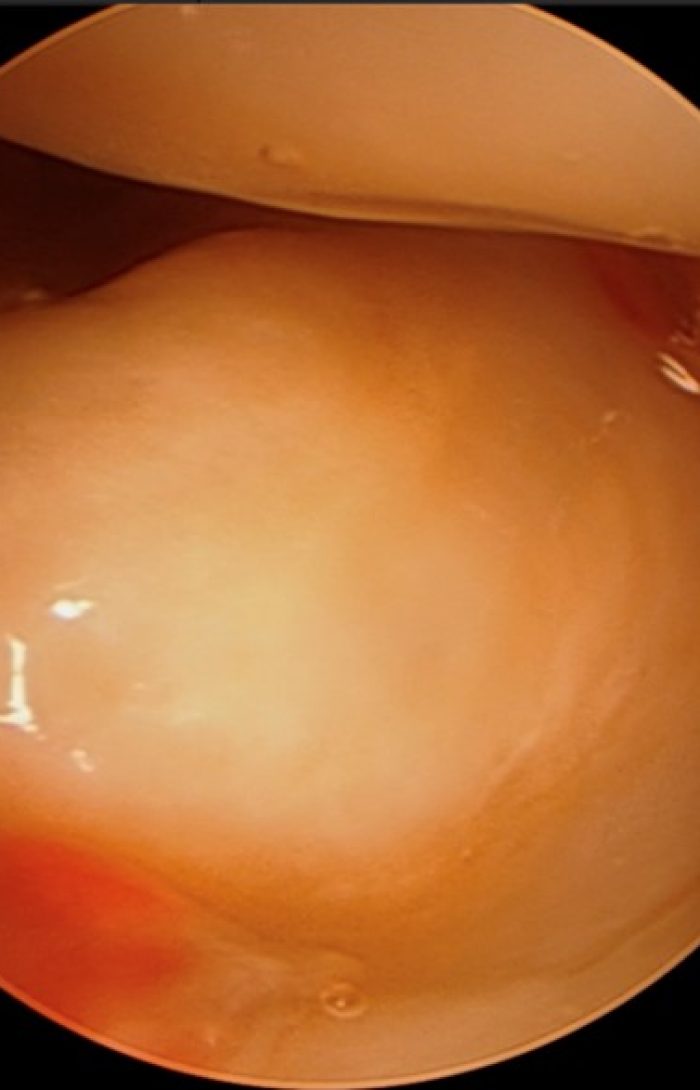

Em lesões mais graves (instabilidade) ou que não respondem ao tratamento conservador, a cirurgia pode estar indicada. A artroscopia do punho permite ao cirurgião reparar ou remover partes danificadas da fibrocartilagem, ajudando a restaurar a função e a estabilidade do punho.